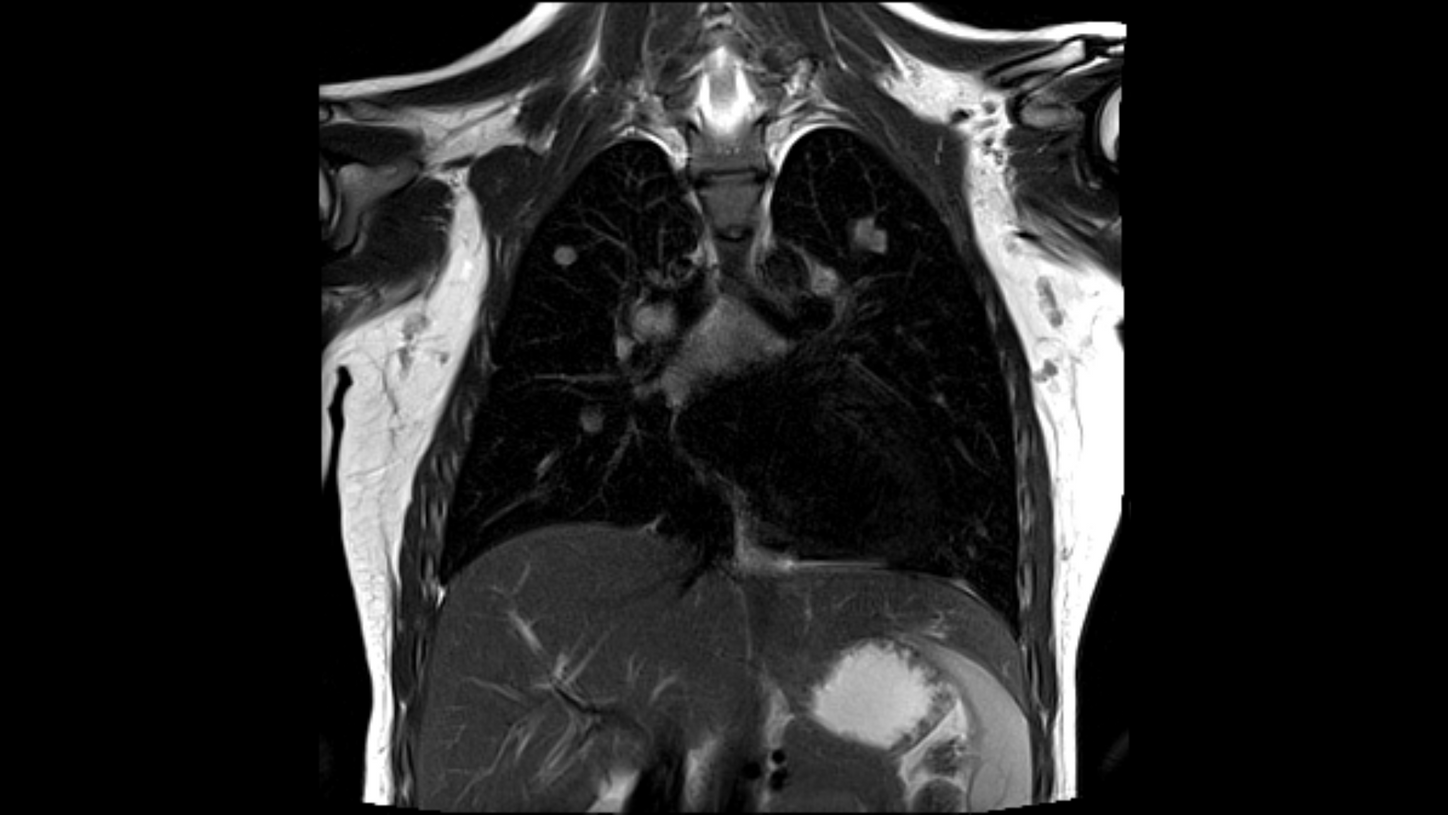

Biograph mMR, StarVIBE | Courtesy: Royal Children's Hospital, Melbourne/VA, Australia | Study-ID: 4aaaa0074

FREEZEit

With our award-winning FREEZEit package – including StarVIBE – you will be able to take pulmonary imaging to the next level by overcoming contrast-agent timing issues and problems with motion. StarVIBE delivers T1-weighted robust, free-breathing, and contrast-enhanced exams for patients by intelligently resisting motion artifacts.

Your benefits:

- Free-breathing T1-weighted 3D measurements with very high spatial resolution

- StarVIBE effectively compensates breathing and other sources of motion artifacts by using a stack-of-stars trajectory

- Entire scan is contrast-sensitive, and contrast enhancement cannot be missed